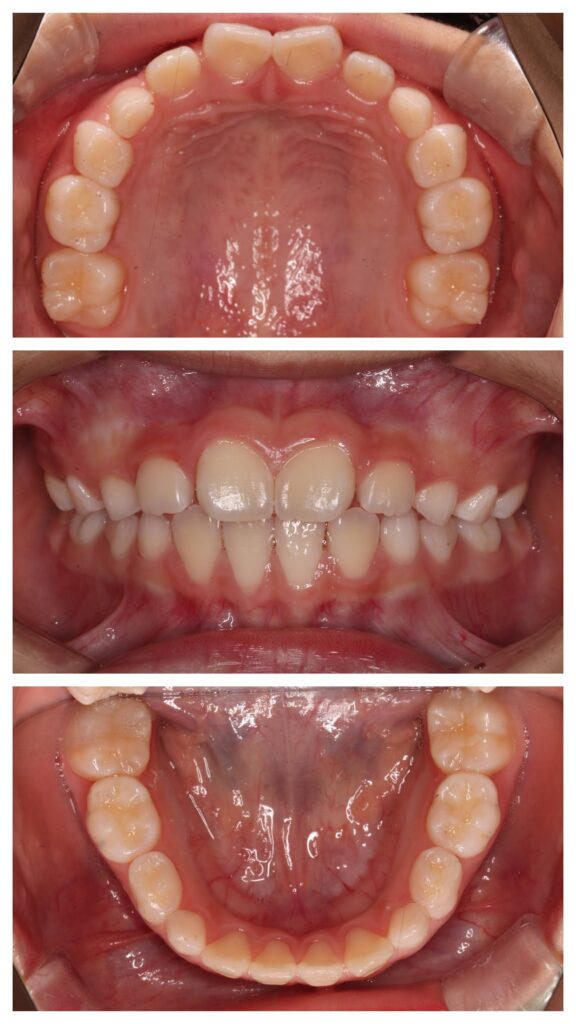

AFTER

歯列はU字型へ拡大。

永久歯が並ぶ余裕のあるアーチへ改善しました。